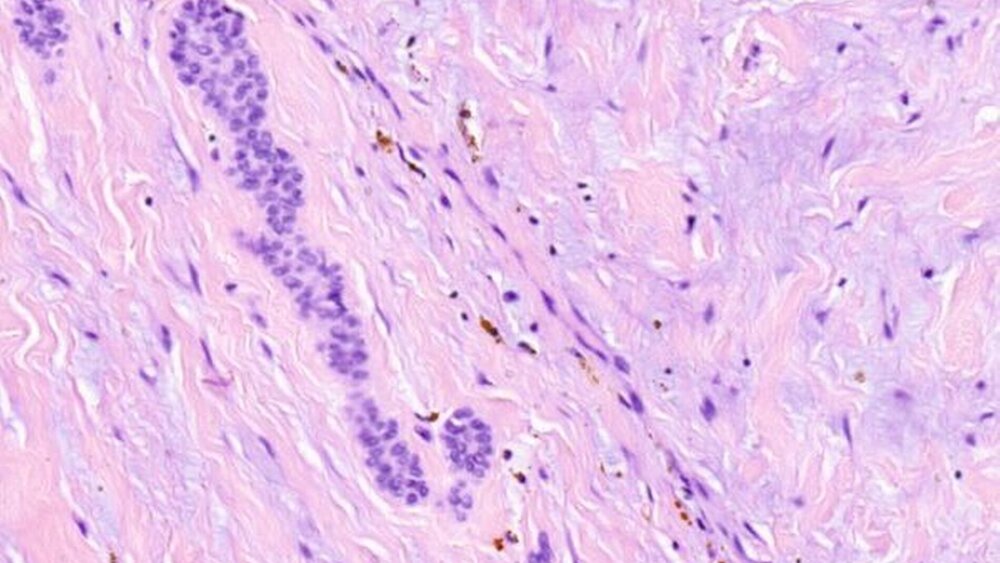

Das histologisch-anatomische Gutachten ergab die Diagnose odontogener Fibrome in der epithelarmen Variante. Im histologischen Bild imponierten spindelförmige Zellverbände, eingelagert einzelne osteoklastische Riesenzellen und vereinzelt kleine epitheliale Komplexe Malassez’sche Nester.

Die aktuelle WHO-Klassifikation unterscheidet zwei histologische Typen des odontogenen Fibroms: eine epithelarme (simple type) und eine epithelreiche (complex type) Variante [Barnes et al, 2005]. Die epithelarme Variante ist eine relativ azelluläre Läsion mit feinem Kollagengeflecht und einem bedeutenden Anteil an Grundsubstanz mit fibromyxoidem Charakter [Barnes et al., 2005]. Dieser Typ kann Anteile inaktiven odontogenen Epithels enthalten, in seltenen Fällen finden sich Kalzifizierungen. Außerdem können dysplastisches Dentin, Zement- oder Knochenbildungen vorkommen [Barnes et al., 2005; Allen et al., 1992; Neville et al., 2009]. Die epithelreiche Variante besteht aus einem dichten zellulären Gewebeverbund. Häufig liegen Fibroblastenansammlungen und weniger zellreiche Areale dicht nebeneinander mit zahlreichen kleinen Blutgefäßen und Inseln versprengter odontogener Epithelzellen. Bei der epithelreichen Variante des odontogenen Fibroms fallen besonders die odontogenen Epithelzellen auf [Barnes et al., 2005; Neville et al., 2009].

Zusammenfassend findet sich beim odontogenen Fibrom – wie im vorliegenden Fall – mikroskopisch bindegewebiges Stroma und – nicht obligat – odontogene Epithelzellnester oder -stränge [Pindborg et al., 1971]. Sonderformen sind das odontogene Fibrom vom riesenzellig-granulomatösen Typ [Allen et al., 1992] und jenes vom Granulartyp [Shiro et al., 1989].